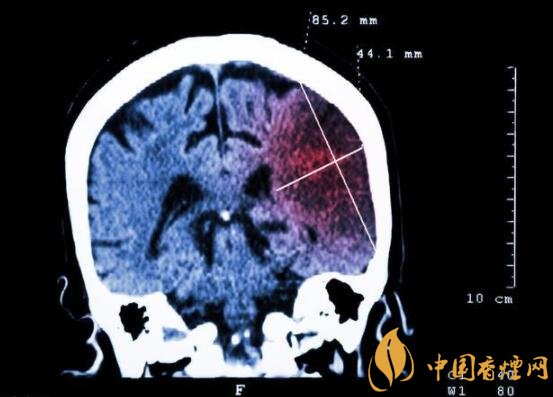

一般而言,急性腦梗塞與長期吸煙有非常密切的聯(lián)系。有長期煙齡遇到肢體活動不順,做頭顱核磁共振檢查往往查出一側(cè)大腦中動脈閉塞的可能性很高。由此可見,吸煙確實(shí)與中風(fēng)存在一定聯(lián)系。